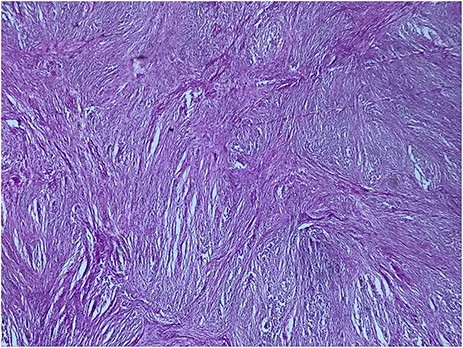

A 73-year-old woman was referred to our general surgery service. Her complain was intermittent gastric discomfort. There was no significant past medical history. There was no history of upper gastrointestinal bleed, or past surgical interventions with no abnormalities found on physical exam. An esophagogastroduodenoscopy (EGD) revealed a submucosal mass in the gastric body. Biopsy of the mass showed no evidence of malignancy. Computerized tomography (CT) scan of the abdomen showed an exophytic solid homogeneous mass along the greater curvature of the stomach and partly projected into the gastric lumen, causing smooth indentation measuring 8 × 8 × 6 cm3 (Fig. 1). The patient’s laboratory results were unremarkable. A presumptive diagnosis of GIST was made. The patient underwent successful wedge resection of the mass through laparotomy and the specimen was sent to pathology. On gross examination, a white intramural, nodular, solid mass measuring 8.7 × 8.8 × 6.7 cm was seen. A cut section revealed whirling trabeculation with a biphasic proliferation of compact hypercellular areas and myxoid hypocellular areas (Fig. 2). Sections from the tumor showed interlacing bundles of spindle cells, which had elongated nuclei, ill-defined cytoplasmic borders and palisading nuclei (Fig. 3). No nuclear atypia was noted. No mitotic activity and no necrosis were identified. There was no lymph node involvement and the surgical margin was negative for tumor cells. A histological diagnosis of a benign mesenchymal tumor was made. Immunohistochemistry (IHC) staining was strongly positive for S-100 (Fig. 4), whereas c-Kit, CD 34; DOG 1; smooth muscle actin (SMA), desmin and AE 1/AE 3 were negative. Hence, a final diagnosis of schwannoma was made. The postoperative period was uneventful and the patient was dismissed from the hospital after 5 days.

A helpful histologic clue to the diagnosis of schwannoma is a peritumoral lymphoid cuff, which is rare in GIST [8]. Schwannoma cells have spindle-shaped nuclei and a fascicular arrangement. The diagnosis of schwannoma is based on immunohistochemical positivity for S-100 protein [1,8]. Our case was misdiagnosed as a GIST until these histological and immunohistochemical findings were revealed.